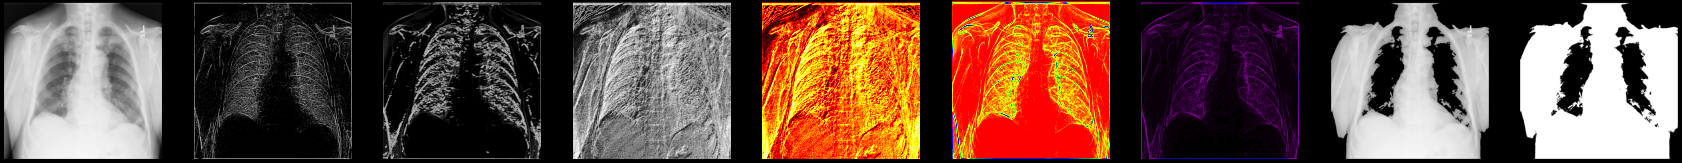

让我们展示一些您迄今为止处理过的X光图像处理结果。

fig, axes = plt.subplots(nrows=1, ncols=9, figsize=(30, 30))

axes[0].set_title("Original")

axes[0].imshow(xray_image, cmap="gray")

axes[1].set_title("Laplace-Gaussian (edges)")

axes[1].imshow(xray_image_laplace_gaussian, cmap="gray")

axes[2].set_title("Gaussian gradient (edges)")

axes[2].imshow(x_ray_image_gaussian_gradient, cmap="gray")

axes[3].set_title("Sobel (edges) - grayscale")

axes[3].imshow(xray_image_sobel, cmap="gray")

axes[4].set_title("Sobel (edges) - hot")

axes[4].imshow(xray_image_sobel, cmap="hot")

axes[5].set_title("Canny (edges) - prism)")

axes[5].imshow(xray_image_canny, cmap="prism")

axes[6].set_title("Canny (edges) - nipy_spectral)")

axes[6].imshow(xray_image_canny, cmap="nipy_spectral")

axes[7].set_title("Mask (> 150, noisy)")

axes[7].imshow(xray_image_mask_noisy, cmap="gray")

axes[8].set_title("Mask (> 150, less noisy)")

axes[8].imshow(xray_image_mask_less_noisy, cmap="gray")

for i in axes:

i.axis("off")

plt.show()